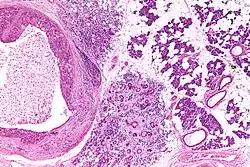

Very high mag.